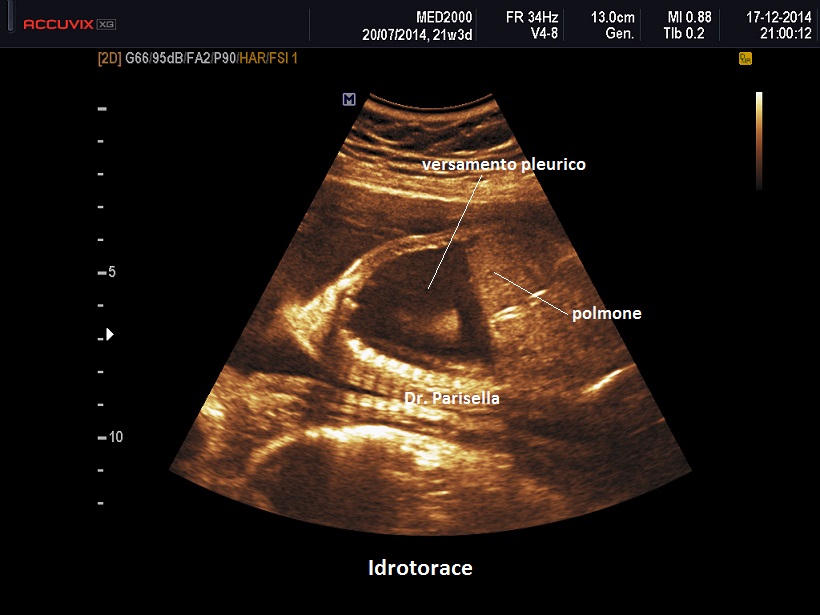

I segni ecografici sono:

• edema del sottocute: spessore > 5 mm.

• iperplacentosi: spessore placentare > 6 cm.

• polidramnios

• ascite

• effusione pericardica

• effusione pleurica

Come detto in precedenza l'accumulo di liquido deve interessare almeno due compartimenti.

Un primo orientamento sulle cause di idrope può essere fatto attraverso la localizzazione dell'accumulo di liquido: un accumulo generalizzato sin dal principio orienta verso una causa sistemica come l'anemia, mentre un accumulo inizialmente localizzato porta ad orientarsi verso una patologia locale ( es.: versamento pleurico >>>> Malformazione Adenomatoide Cistica Congenita del polmone).